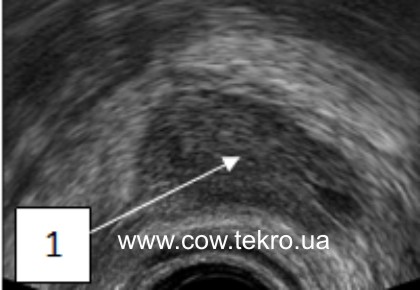

За ультразвукового дослідження гонад корів мають однорідну ехоструктуру, нормальні розміри, кількість везикульрних фолікулів зменшена, а жовті тіла відсутні (рис. 2).

Рисунок 2 –Ехограма яєчника корови за гіпофункції: 1 – тканинии яєчника